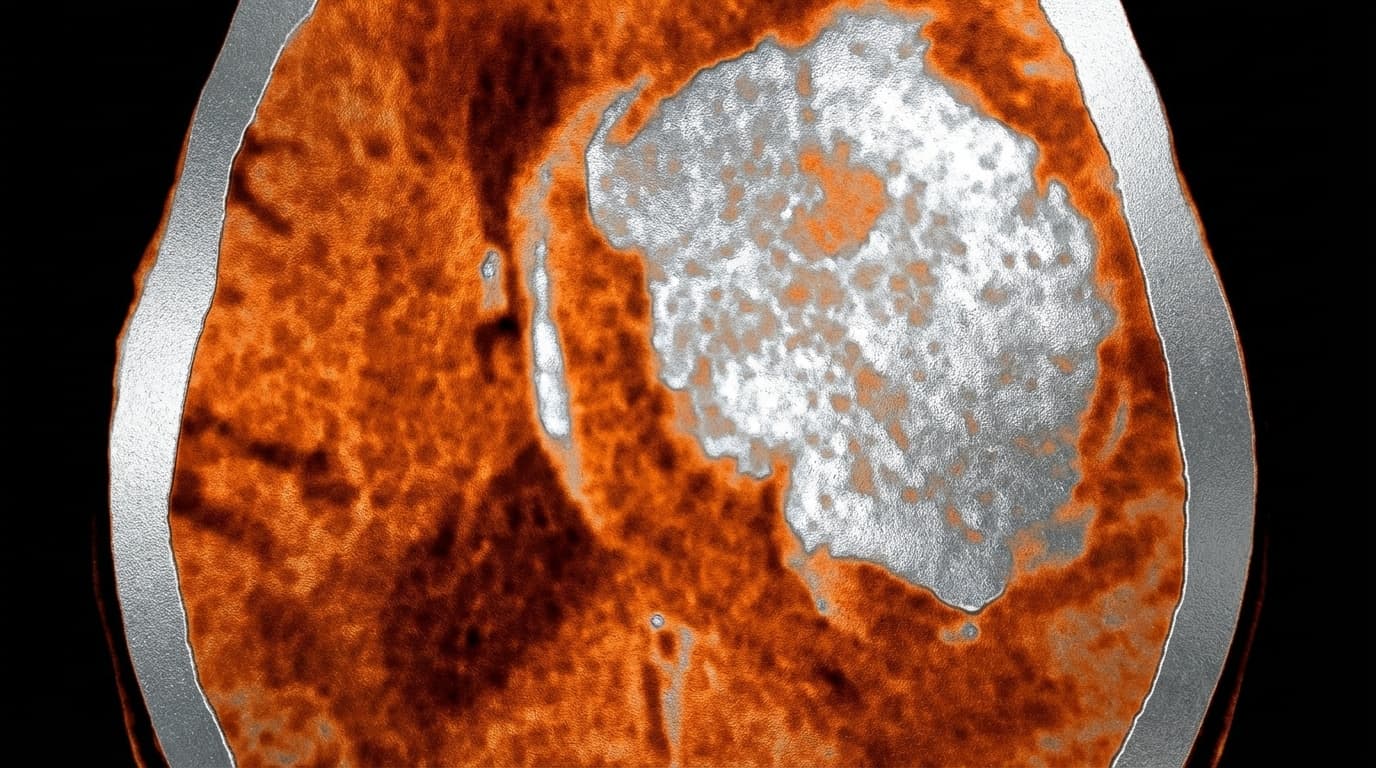

🩸🧠 Hemorragia Intraparenquimatosa (HIC)

Sangramento diretamente dentro do tecido cerebral (miolo do cérebro), geralmente causado por pressão alta crônica não controlada que enfraquece pequenos vasos até eles estourarem. É como um cano estourando dentro de uma parede. Também pode ocorrer por amiloidose em idosos, anticoagulantes ou malformações vasculares. O sangue ocupa espaço, comprime o cérebro e causa edema ao redor.